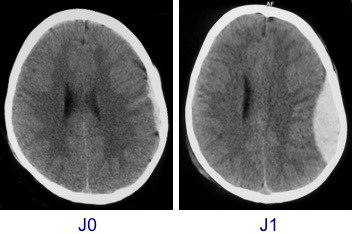

si l’HED a été opéré au stade d’engagement, l’évolution peut malgré tout être très favorable (cf. ci-contre), mais le patient risque de garder des séquelles liées à la souffrance cérébrale aiguë, parfois à une compression vasculaire.

- avec un second scanner de contrôle à 6 heures du précédent ; s’il est stable, on peut se contenter ensuite d’une surveillance clinique